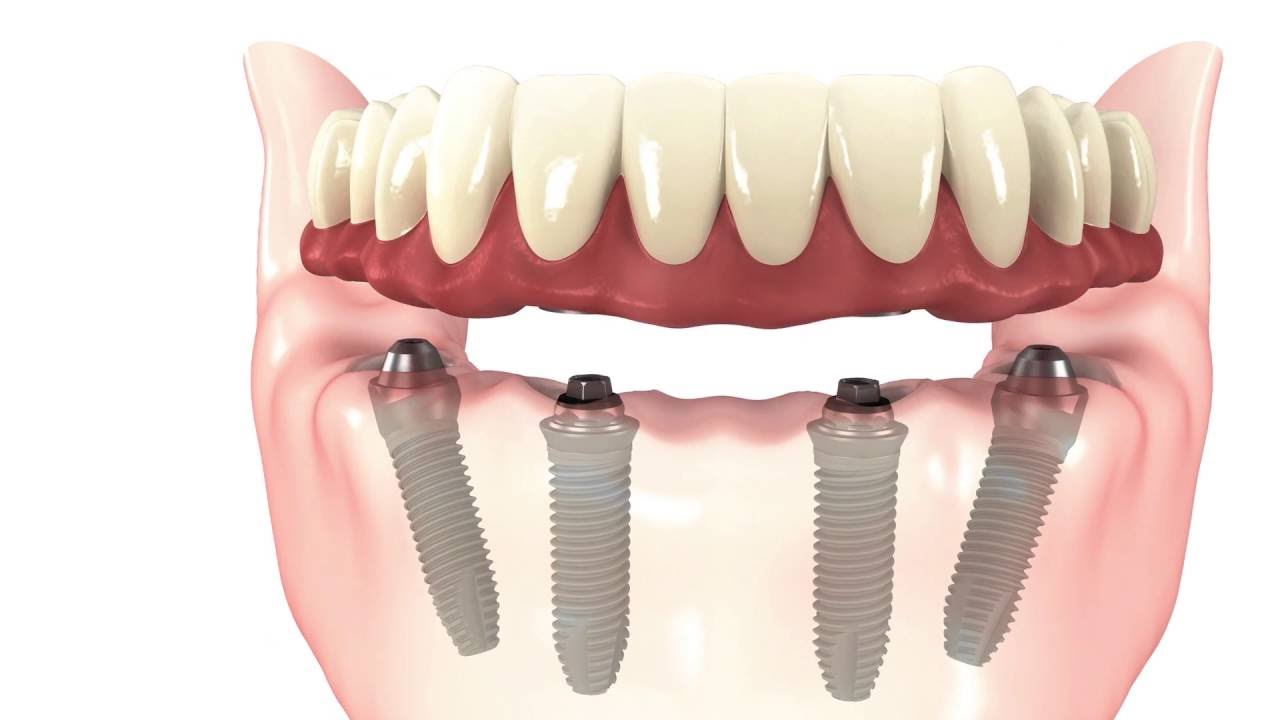

All-on-4

Dental Implants

Full Arch Restoration

Teeth in a Day

Dr Khattak has experience of over 15 years in dental implant solutions and we can arrange a free implant consult after your dental checkup. Dental implants can easily replace missing teeth and also help in better retention of dentures. We also provide full arch dental implants to replace lost teeth with implant supported bridges which are often referred to as ‘teeth in a day’ , All on four, AO4 or ‘teeth express’.